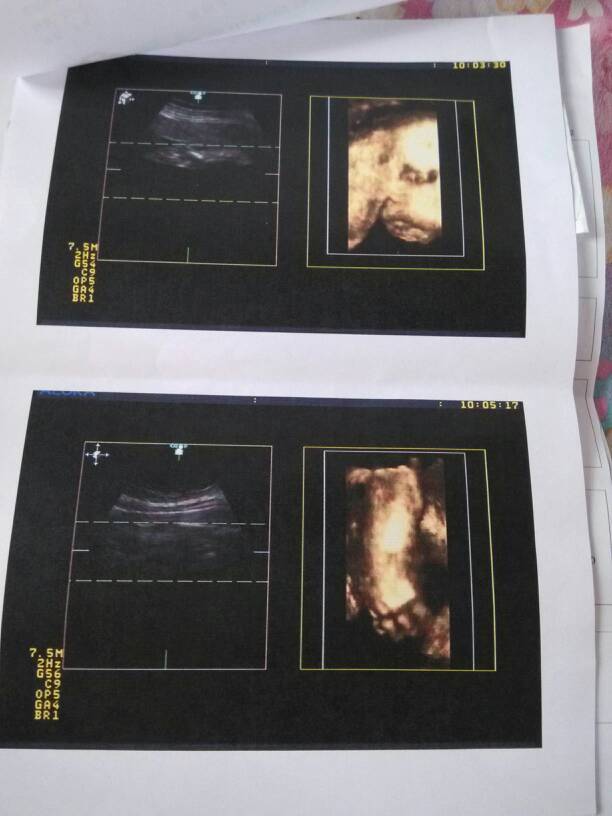

为什么我今天做得四维彩超只有图片和一张B超单子 没有像别人做的那种有写大脑 肾 心脏什么得这些说 为什么我今天做得四维彩超只有图片和一张B超单子 没有像别人做的那种有写大脑 肾 心脏什么得这些说明 难道我得不是四维彩超? 点击展开 梦的点滴 2014-09-15 13:31 为您推荐: 其他回答 噢!原因是这样 137*****360_vnzM 2014-09-15 19:53 啊,那这样要多少钱啊?我的都写得清清楚楚噢 137*****360_vnzM 2014-09-15 14:15 我的也没写,放心吧如有问题医生会告诉你的 针刺人心灸更深 2014-09-15 13:39 相关问题 今天去预约四维彩超,医生不给打B超单子,我在机子上看到写的脊柱双肾,请问这是什么意思啊? 我怀孕25周了,去照四维彩超,B超显示宝宝左肾肾盂分离0 53厘米,右肾肾盂分离 24周的时候,做的四维彩超单子上说,胎儿双肾盂分离,右肾,肾盂分离0 7cm,左肾,肾盂分离0